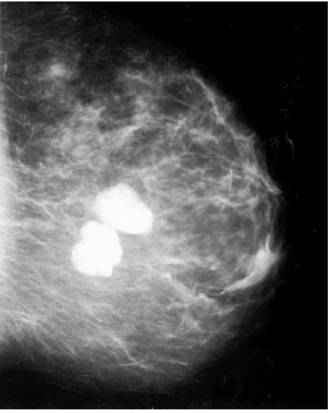

בממוגרפיה הכיסיות המיקרוסקופיות נראות לעתים כהסתיידויות זעירות, הנראות כמו נוזל בתחתית של ספל ונקראות "Milk of calcium" (תצלום 15.12).